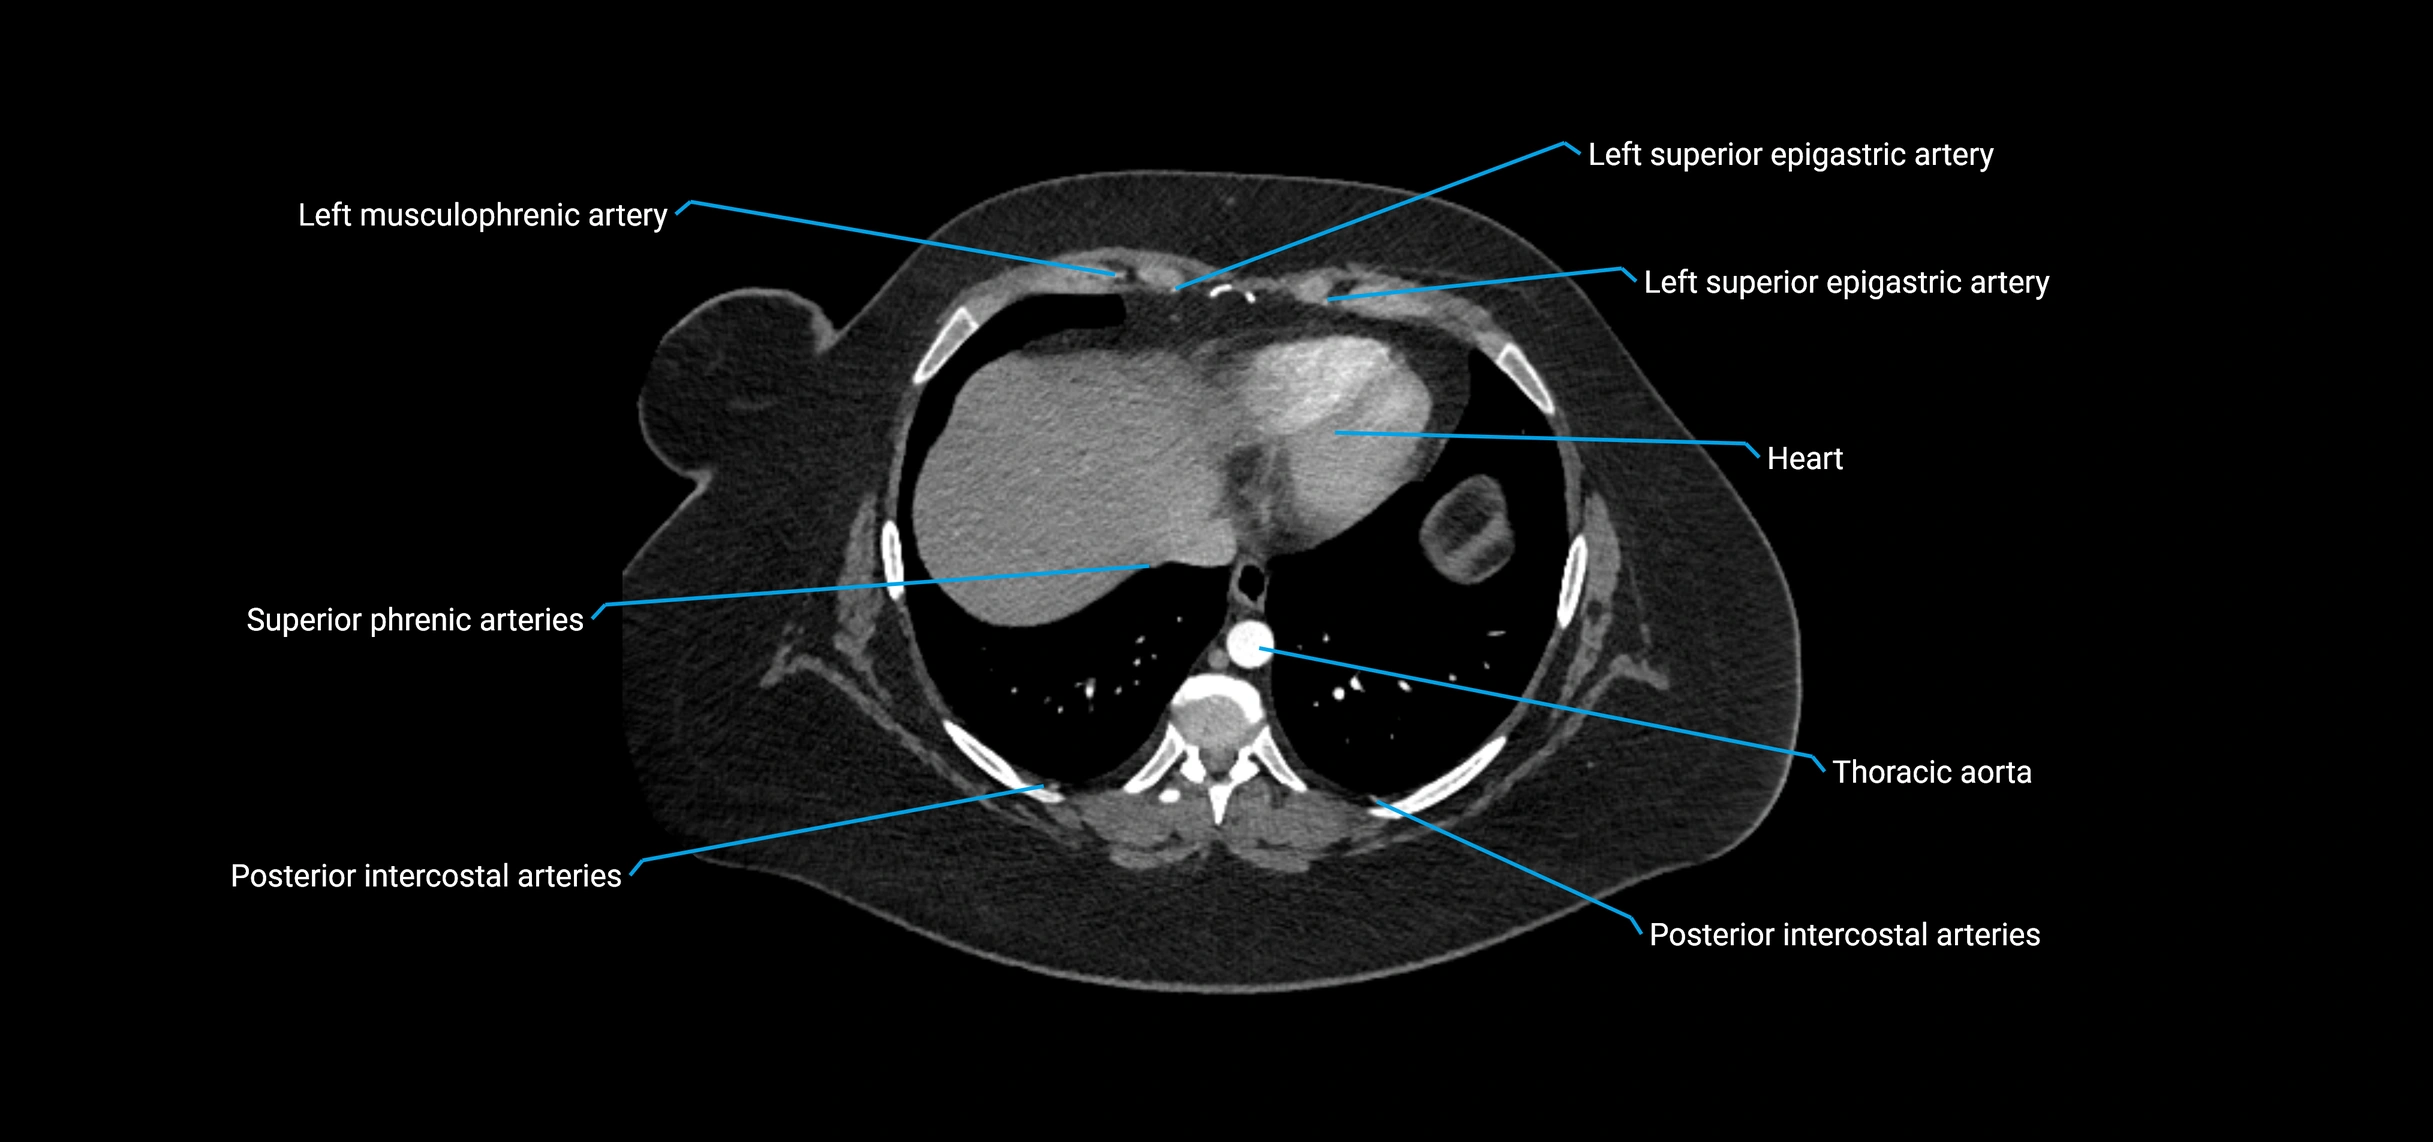

Contrast-enhanced CT (CTA):

• Gold standard for abdominal aortic imaging

• Provides excellent detail of lumen, wall, aneurysm, thrombus, and branch vessels

• Multiplanar and 3D reconstructions help in aneurysm measurement, stent graft planning, and dissection evaluation

• Detects acute rupture, traumatic injury, or occlusion with high sensitivity